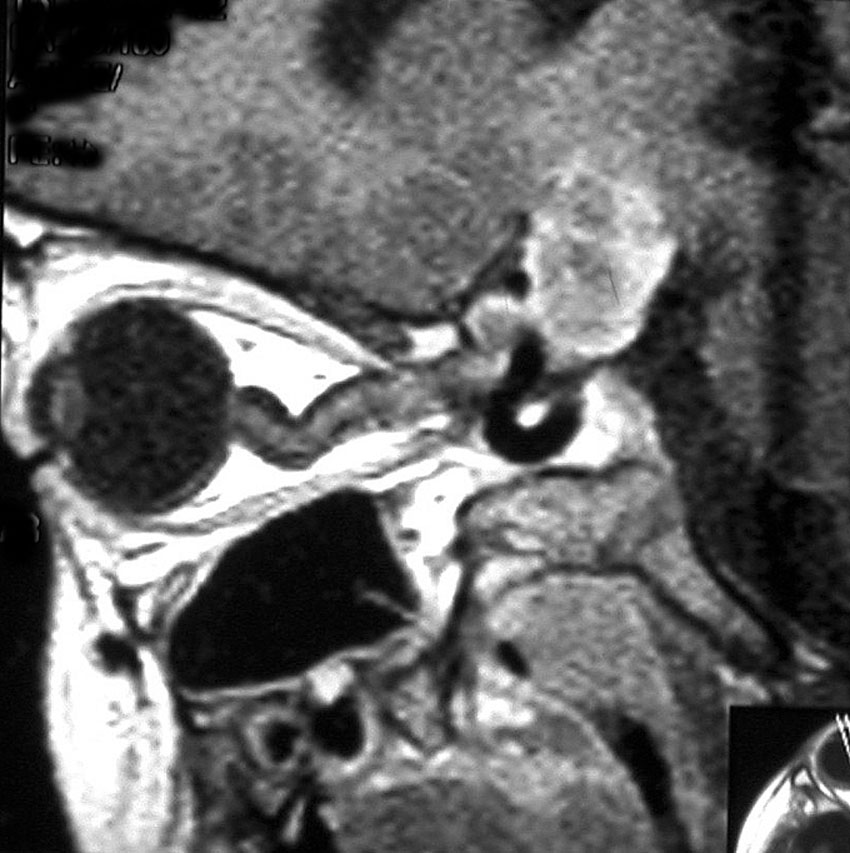

視索に限局する毛様細胞性星細胞腫

左の視索の内部から発生したもので,これも単神経・視神経膠腫と同様によくみるものです。左の画像で視神経交叉が全く侵されていないのがわかります。

単視神経膠腫は全摘出できるのですが,このタイプは外側膝状体へ及ぶので完全摘出ができません。部分摘出と定位放射線治療が適応となります。